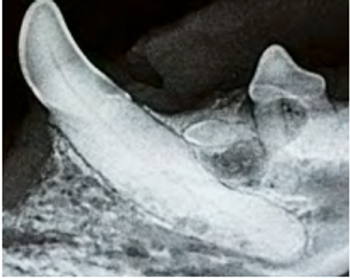

Understanding how tooth resorption is diagnosed and classified enables you to provide better patient care and to increase patient comfort.

Most of the tooth is located below the gumline and out of view. Intraoral radiography can yield invaluable diagnostic information about your patients’ oral health.